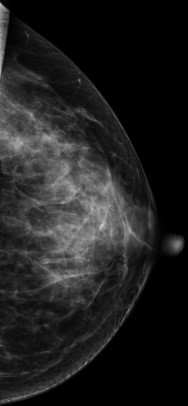

V-preview图像:

常规2D图像在MLO位上象限发现靠近胸大肌处见一不对称团块影,CC位上并没有发现明显肿块影,右乳外象限局部结构较乱,DBT图像左乳外上象限清晰可见一不规则肿块影,呈分叶状,与周边腺体组织界限欠清

影像诊断:

左乳外上肿物--考虑良性可能性大BI-RADS 3级